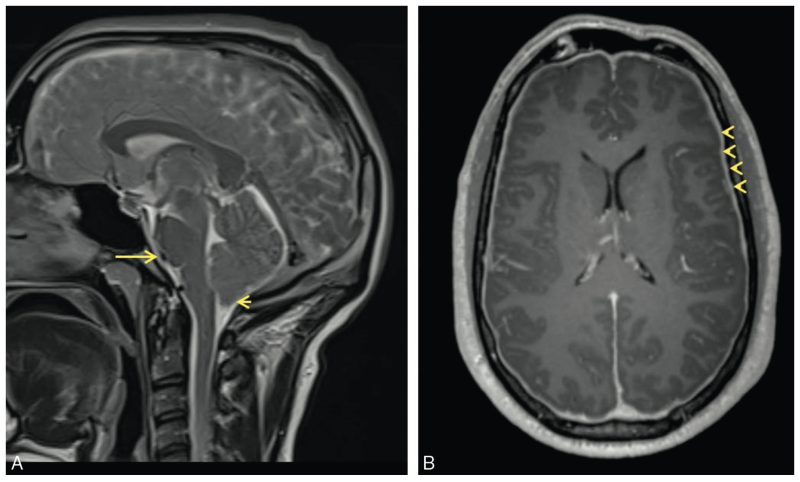

A. T2: Effacement de la citerne pré-pontique (flèche longue), discrète ptose de l'amygdale cérébelleuse (flèche courte)

B. T1 C+: prise de contraste diffuse et régulière des pachyméninges (têtes de flèches)